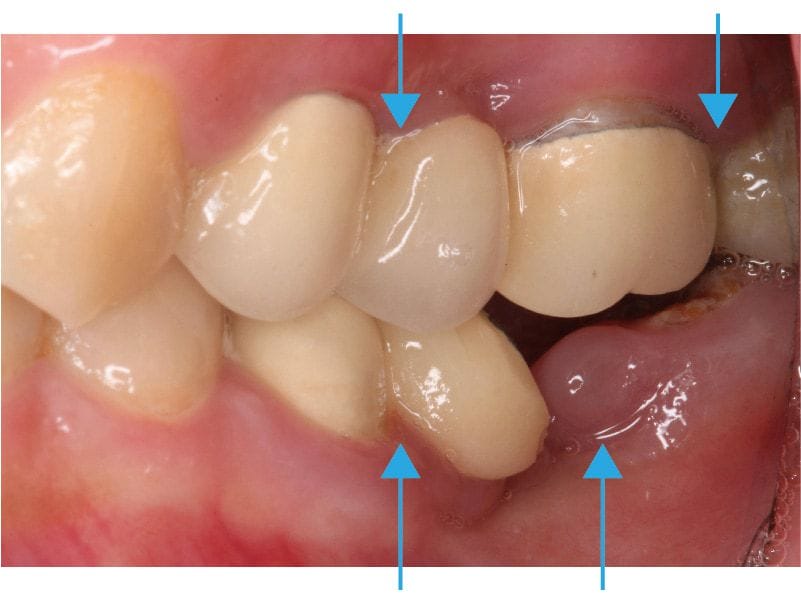

圖示:左下後牙區的假牙和臼齒殘根 圖示:左下後牙區X光片,箭頭處為假牙與臼齒殘根

這可能是因爲是她早期左下的臼齒缺牙,當時在其他診所是用傳統牙橋修復。

傳統牙橋的缺點除了是前後牙齒需要犧牲齒質磨小才能印模製作以外,牙橋底下也會產生清潔死角,導致難做到良好的清潔,很容易發生再蛀牙或是牙周疾病等後遺症,久而久之後面的牙齒蛀斷了成為殘根。